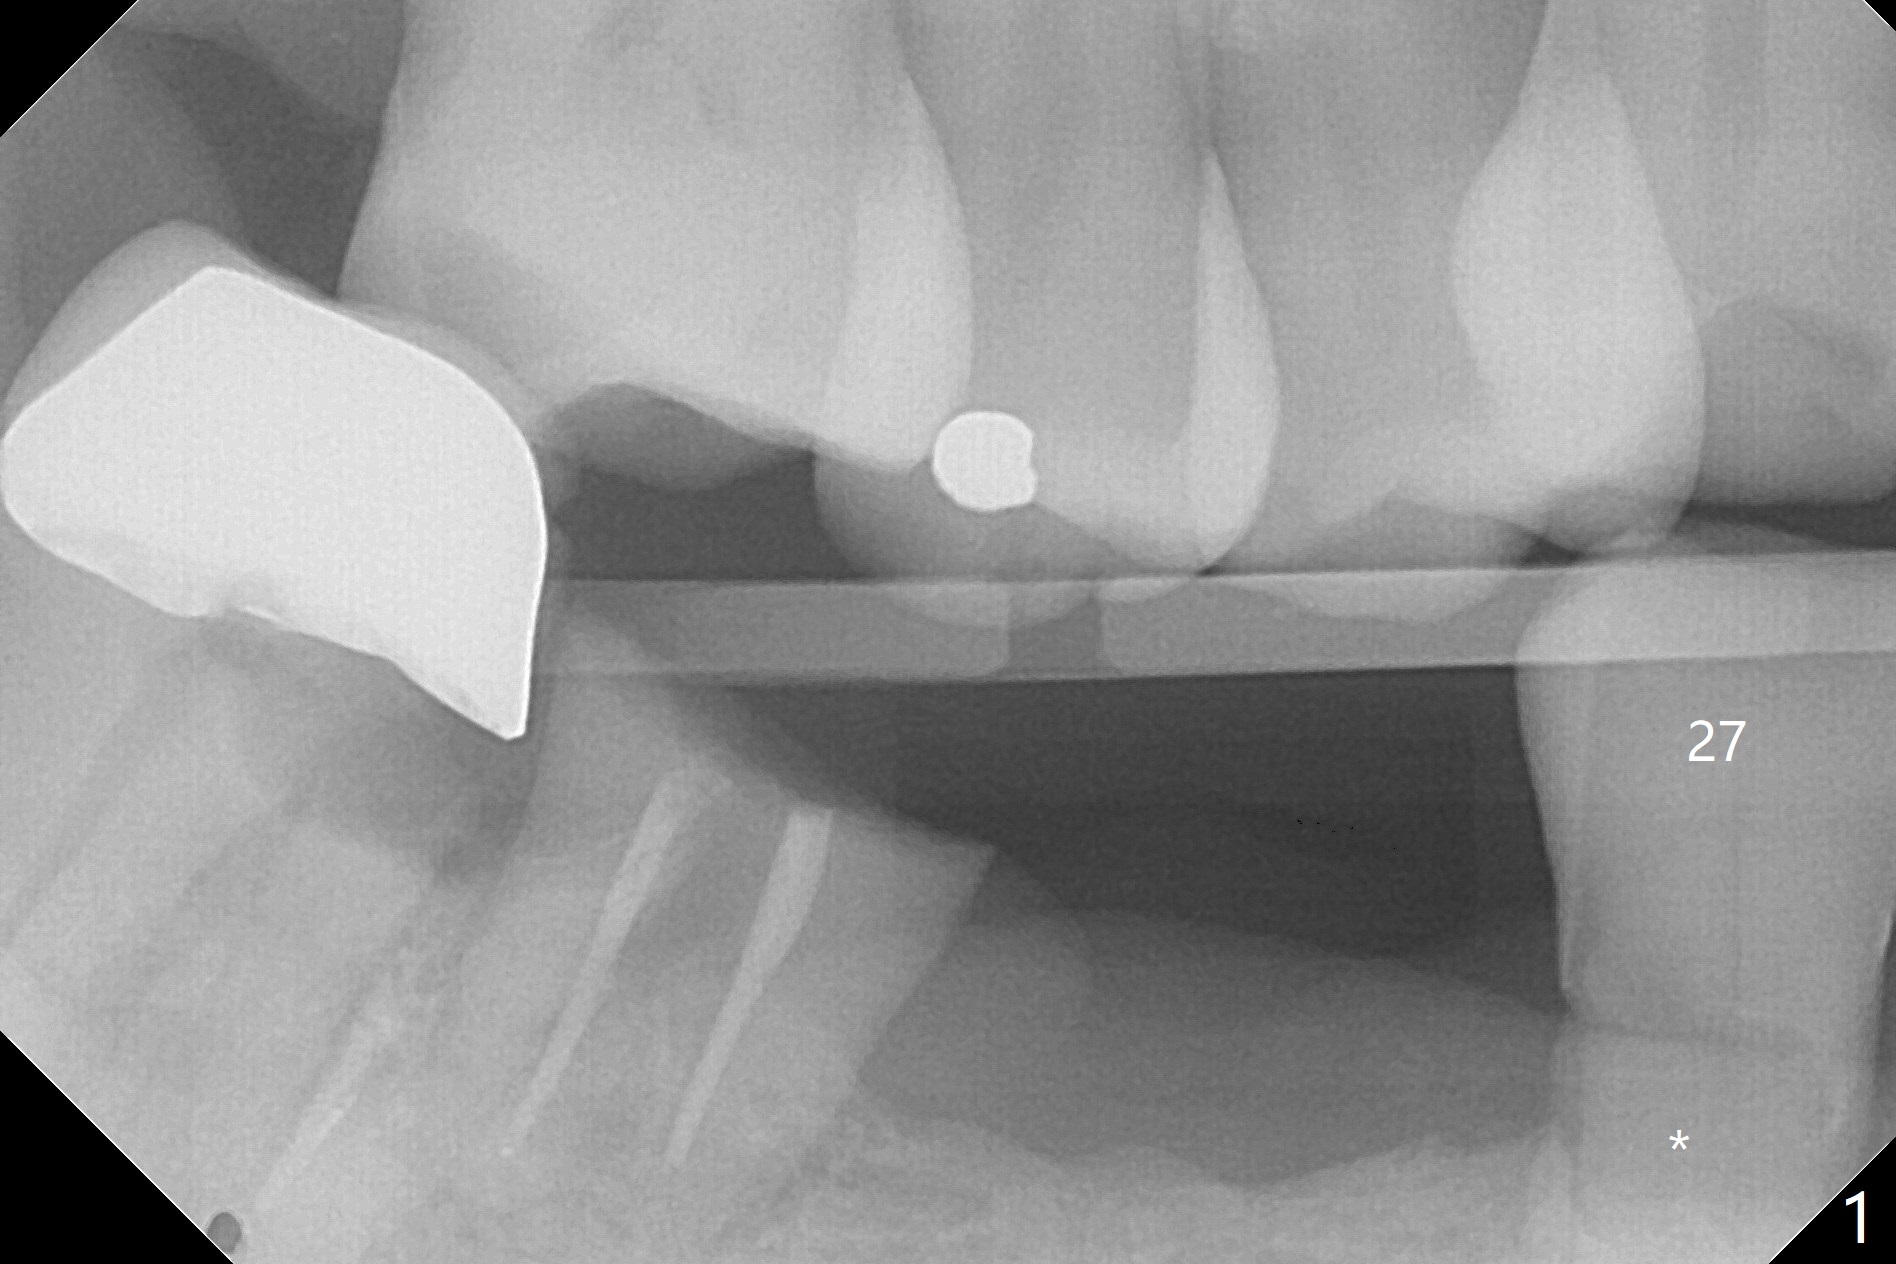

A 63-year-old man requests repair of Class V caries at #27 (Fig.1,2 *). With local anesthesia, Diode laser is used for gingivectomy for composite (Fig.3 C).